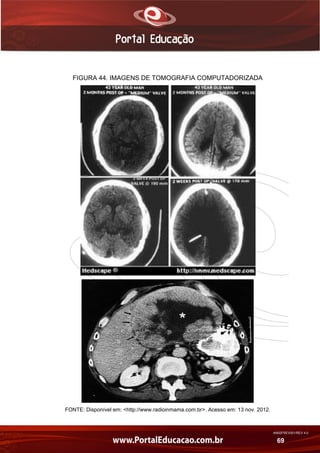

Na figura 44 temos alguns exemplos de imagens de tomografia

computadorizada.

FIGURA 44. IMAGENS DE TOMOGRAFIA COMPUTADORIZADA

FONTE: Disponível em: <http://www.radioinmama.com.br>. Acesso em: 13 nov. 2012.